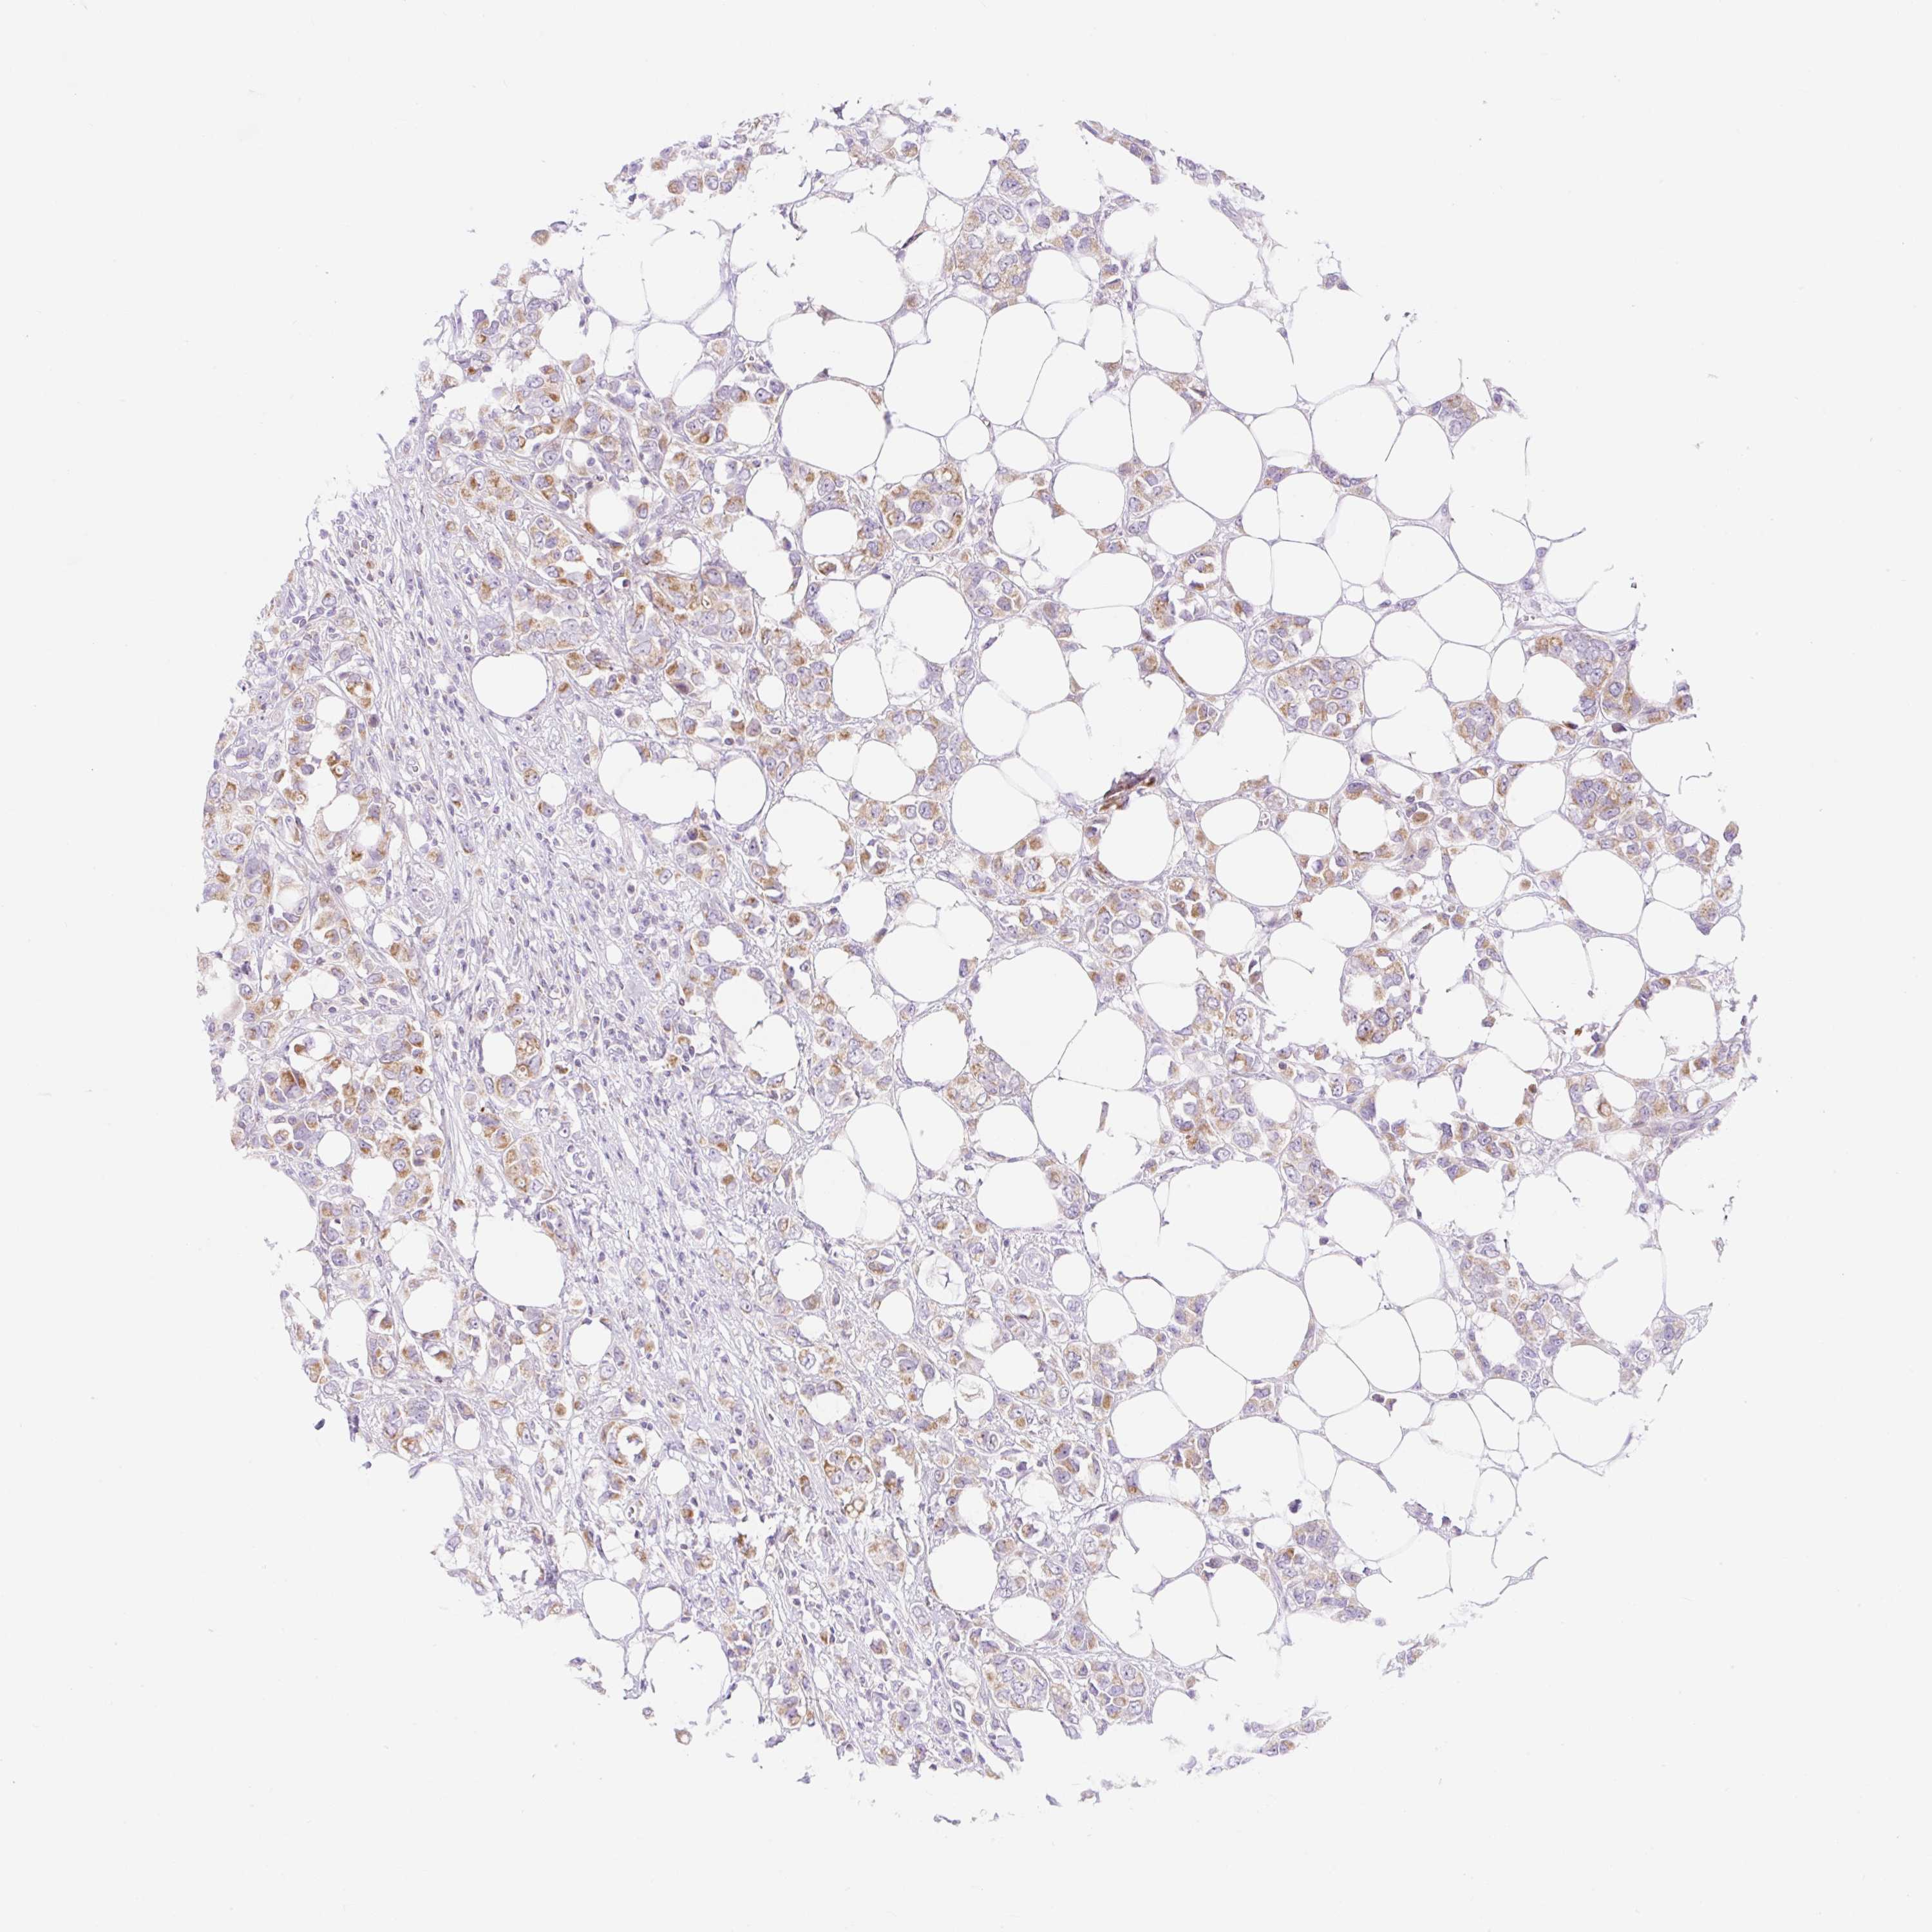

CANCER BREAST CANCER Show tissue menu

BRCA TCGA BRCA VALIDATION PROTEIN EXPRESSION